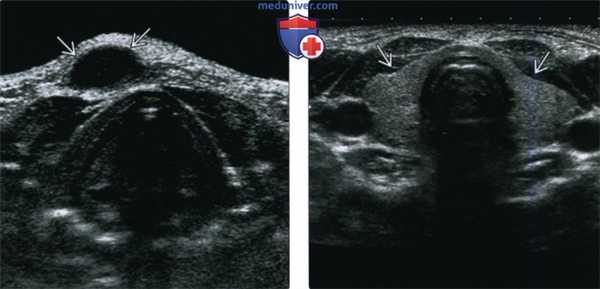

(Слева) На поперечной сонограмме в подкожных тканях визуализируется гипоэхогенное объемное образование с ровными краями, расположенное парамедианно справа, спереди от подподъязычных мышц. Образование было оперативно удалено, подтвердилась КЩЯП.

(Справа) На поперечной сонограмме у ребенка с подозрением на кисту щитоязычного протока в области предполагаемой локализации в нижних отделах шеи визуализируется щитовидная железа, имеющая нормальный вид (состоящая из двух долей). У всех пациентов, обследуемых на предмет КЩЯП, важно документально отразить наличие щитовидной железы в ожидаемом месте и отсутствие патологических изменений с ее стороны.

4. УЗИ при кисте щитоязычного протока:

• Анэхогенное или гипоэхогенное срединное образование шеи:

о ± внутренние эхогенные включения (±кровоизлияния или инфекция):

о Наличие эхогенных включений внутри кисты не соотносится с гистологическими признаками кровоизлияния или инфекции

• При исследовании нижних отделов шеи необходимо убедиться в отсутствии патологических изменений щитовидной железы, наличии обеих долей

(Слева) УЗИ в поперечной плоскости у ребенка с вновь появившимся объемным образованием передних отделов шеи слева: визуализируется патологический гетерогенный очаг без признаков кровотока при цветовой допплерографии, но с выраженными эхогенными включениями, наличие которых позволяет заподозрить дермоид или рак в КЩЯП. При патоморфологическом исследовании подтвердилась киста, не осложненная кровоизлиянием, инфекцией, без признаков наличия злокачественной опухоли.

(Справа) УЗИ в поперечной плоскости у восьмилетнего ребенка: визуализируется типичная подподъязычная КЩЯП в виде анэхогенного объемного образования, расположенного парамедианно и обусловливающего легкое сдавливание левой доли щитовидной железы, в остальном выглядящей нормальной.